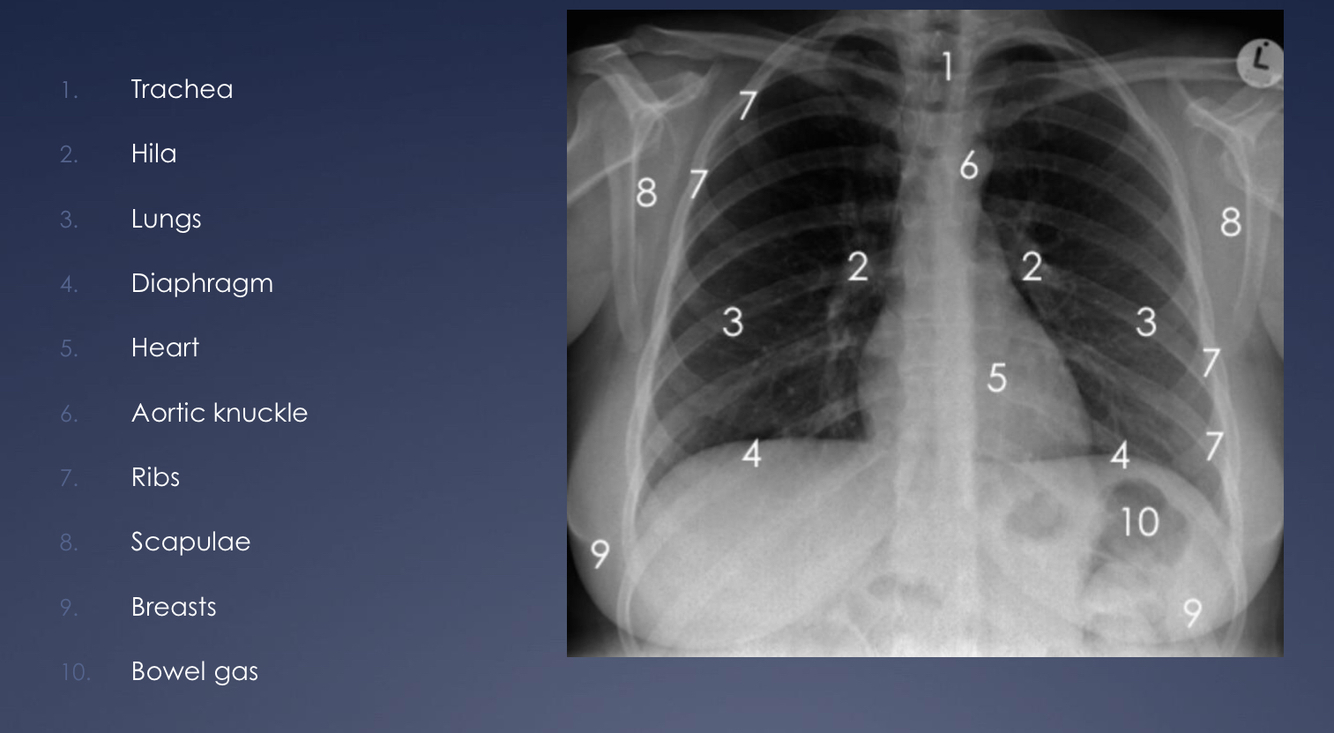

Identify the following anatomical structures